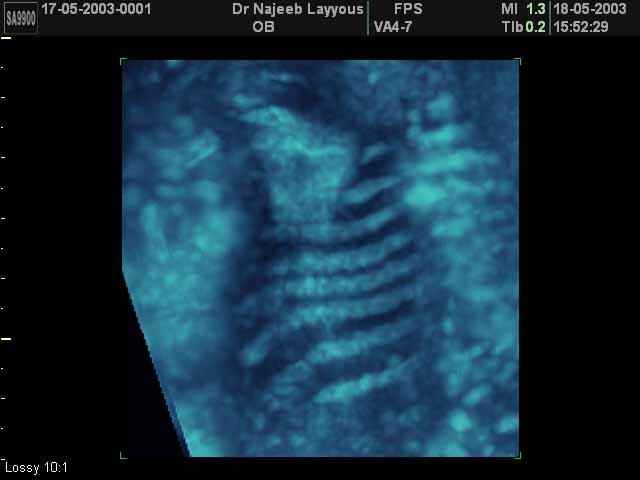

- 3D Photos échographie du squelette du fœtus